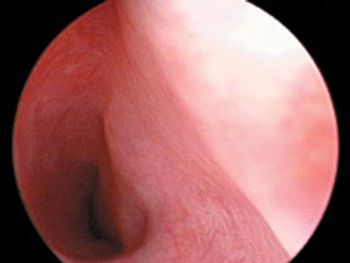

A 7-month-old intact male Labrador retriever was presented for evaluation of a two-week history of left hindlimb lameness.